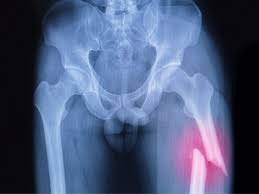

Fracturas

Una fractura es la perdida de

continuidad de un hueso, producida por una fuerza mayor a la que el hueso puede

sostener.

Tipos de fractura:

Fractura abierta:

Las fracturas

abiertas son debidas a una mayor violencia del traumatismo por lo tanto, hacen

prever un mayor número de complicaciones. Se produce un mayor grado de

contusión de las partes blandas, como son los vasos, los nervios y,

fundamentalmente, los músculos y la piel.

Fractura cerrada:

Una fractura cerrada describe una lesión en la

que el hueso roto no penetra la piel. Las fracturas cerradas se mantienen

internas, pero el dolor que causa puede hacer deducir que se trata

efectivamente de una ruptura.